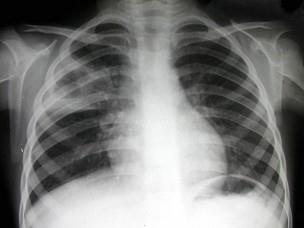

问题 女,10岁,高热、咳嗽一天,血象:中性多形核粒细胞高度增多及核左移,血沉加速,痰中查到大量结核杆菌。结合图片,最可能的诊断是?(?)

选项 A.右上肺干酪性肺炎 B.大叶性肺炎 C.支气管扩张 D.小叶性肺炎 E.葡萄球菌性肺炎

答案 A